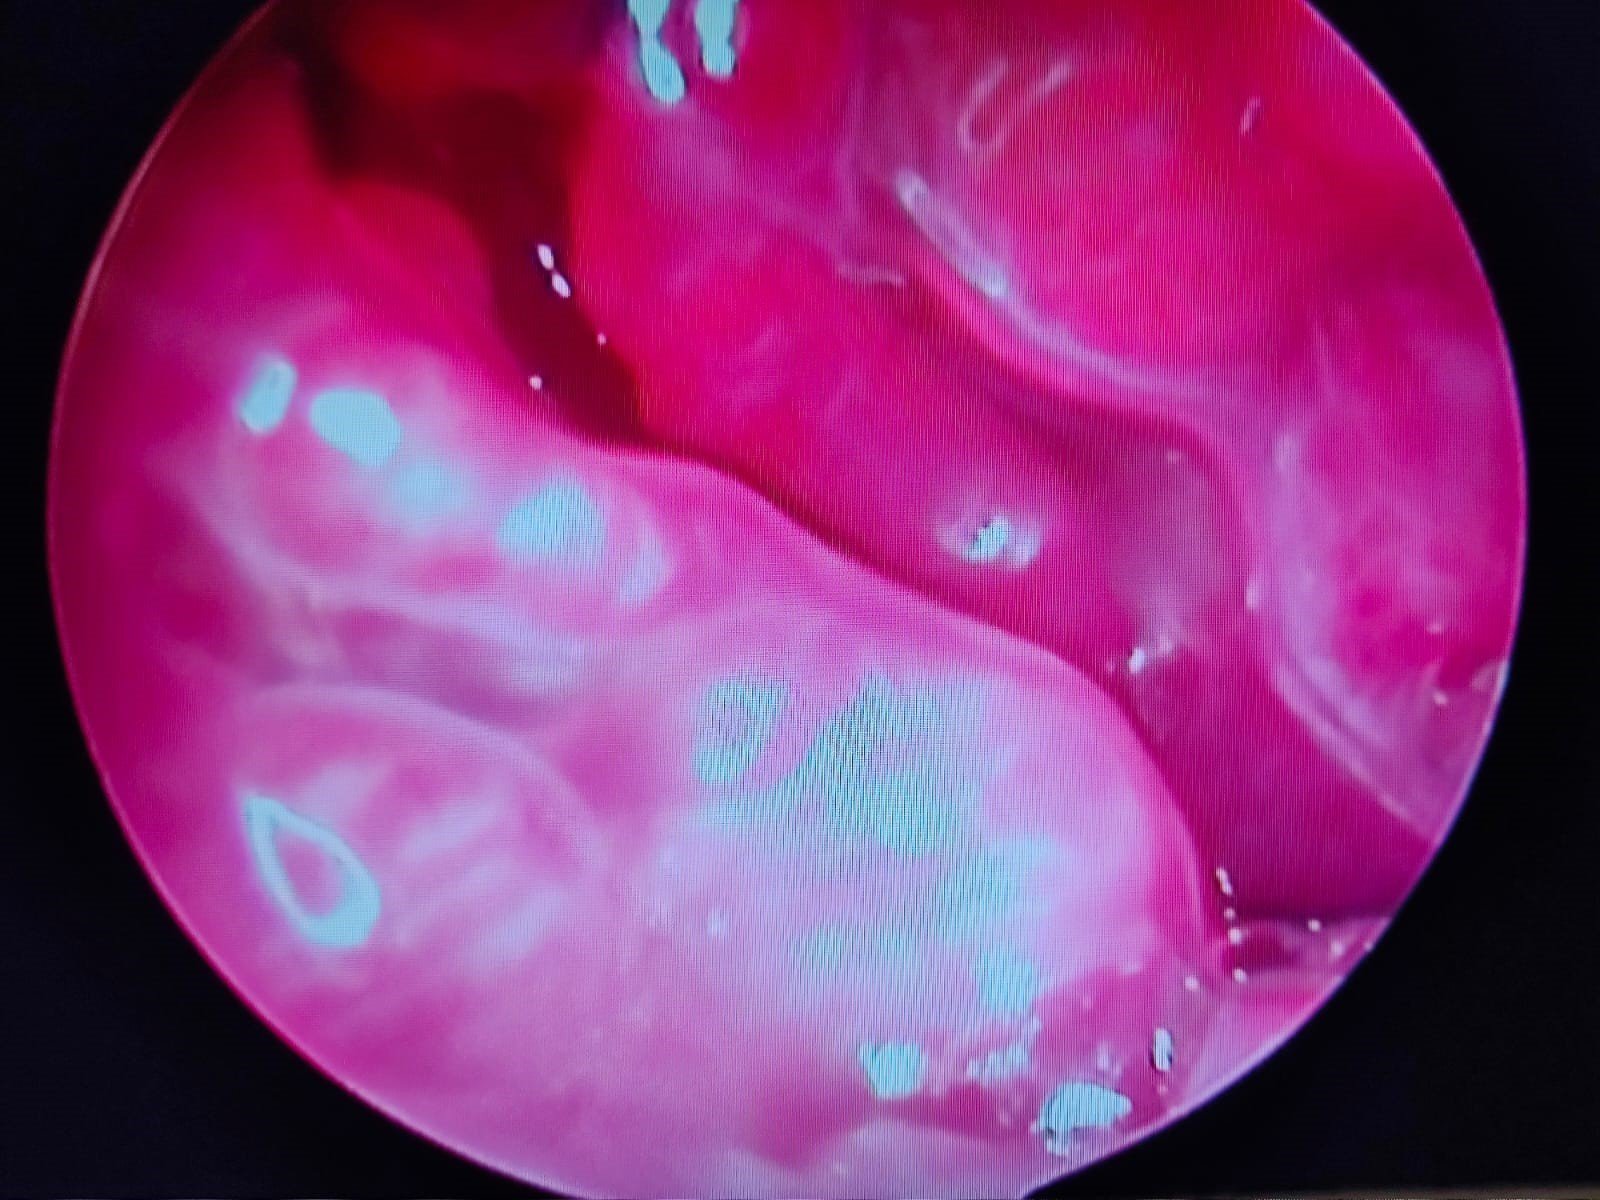

La video otoscopia è un ausilio diagnostico fondamentale nelle indagini del canale auricolare in corso di otiti e corpi estranei. Tramite questo strumento si rende possibile l’asportazione di materiale patologico all’interno dell’orecchio e l’esame completo del canale auricolare e del timpano. La tecnica viene eseguita in anestesia generale per ottenere il miglior risultato senza dolore per il paziente

Lavaggio auricolare in otoscopia per otite cronica